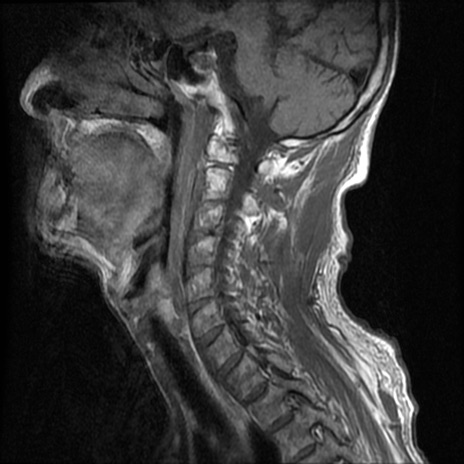

症例46 頚椎MRI T1WI(矢状断像)

【症例】80歳代男性

【主訴】両側頚部〜上肢のしびれ

【現病歴】昨日、自宅内で転倒、その後より上記症状あり。意識障害なし。

【身体所見】両側上肢のallodynia(熱痛覚過敏)あり。MMTおよびDTRは正確な所見取れず。両上肢の挙上はなんとか可能。

異常所見と診断は?